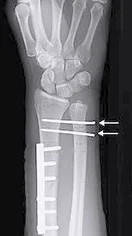

Galeazzi Fracture/ Dislocation

Fracture of the radius with dislocation of the distal radio-ulnar joint

“Fracture of necessity”

- Necessitates surgery

“Fracture of necessity”:

- Plating of radius

- Reduction of distal radio-ulnar joint (+/- Fixation)